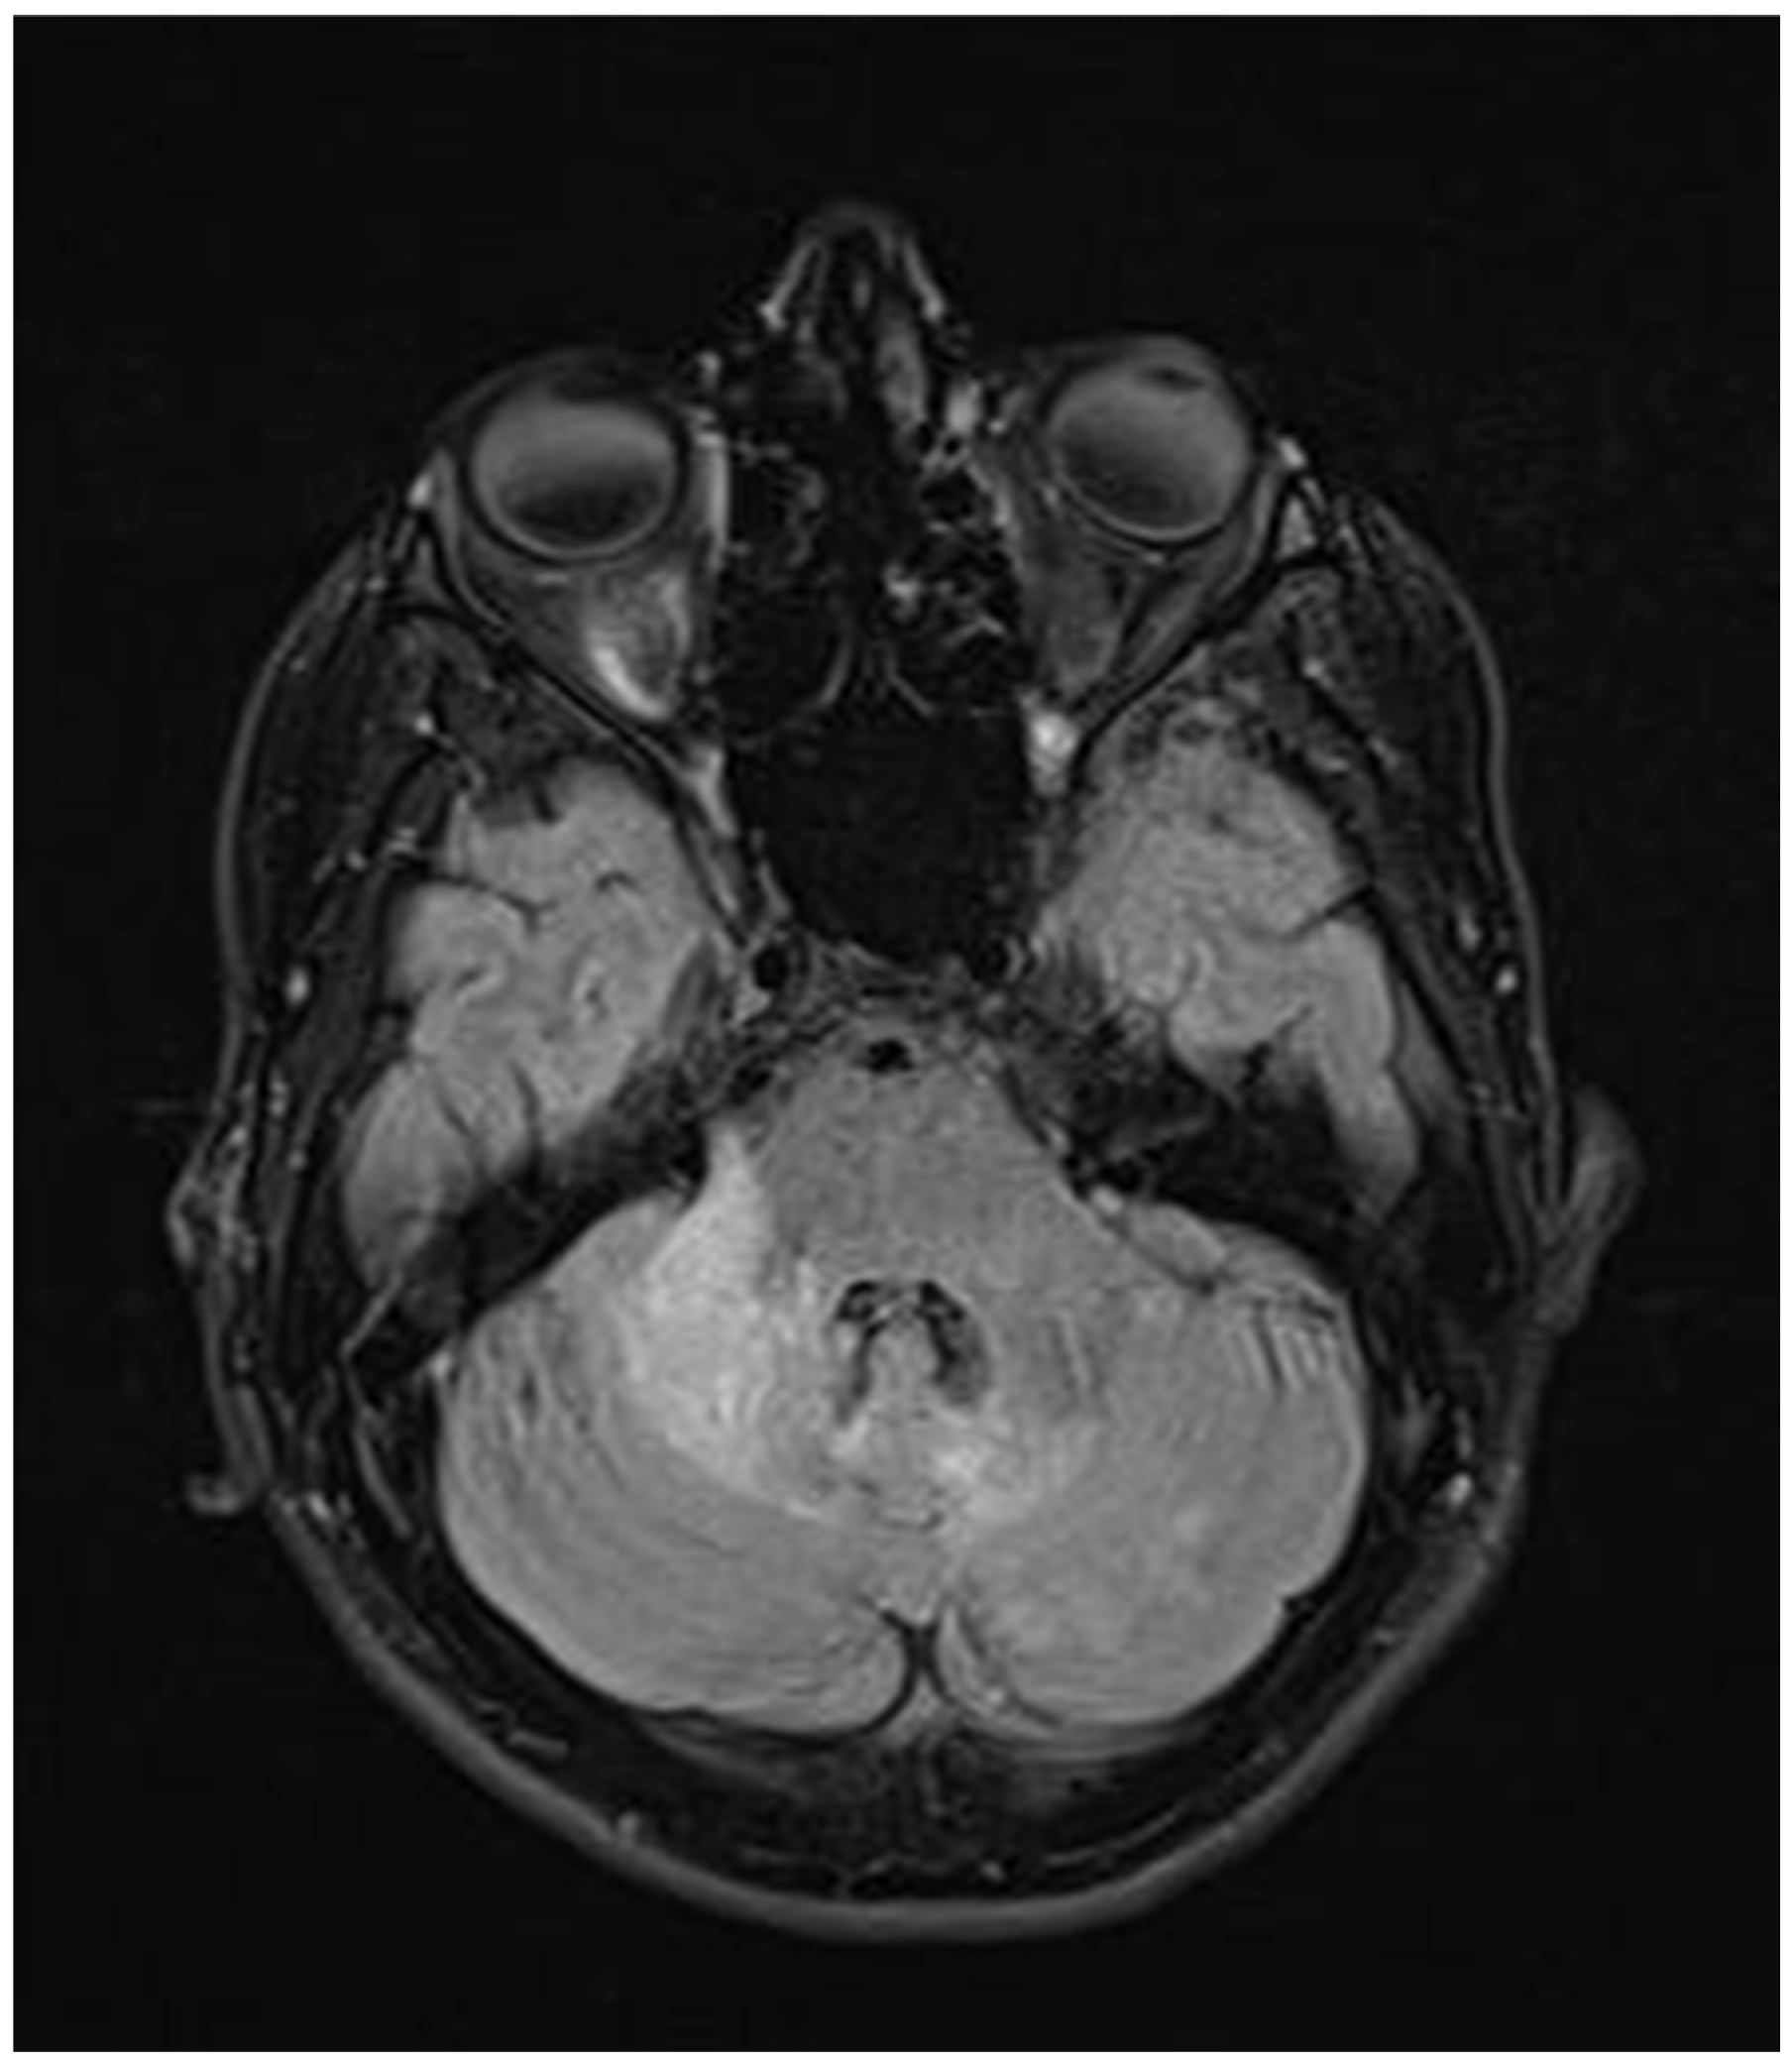

During hospitalization in the neurology ward, Holter EEG was performed in which seizure episodes corresponded to changes in the recording. Interictal EEG showed rapid activity followed by slow theta waves and several sharp and slow wave complexes (Figure 1 and Figure 2). Topiramate was added to valproic acid at a target dose of 2 mg/kg of body weight. Gradual seizure relief was observed in the following weeks, and there were no other neurological manifestations for another nine months. After that time, in December 2021, the patient was admitted to the pediatric ward due to impaired consciousness and persistent vomiting, followed by paresis of the lower limbs. A brain MRI was performed, which showed “T2/FLAIR images reveal poorly defined areas of increased signal in the brain’s white matter, both above and below the tentorium, as well as in the periventricular and subcortical regions. These areas correspond to low signal regions in T1 images. The largest change area measures 19 × 14 mm and is located in the right middle cerebellar peduncle, which merges with changes observed in the pons. Additionally, there is a lesion in the right thalamus, measuring 10 × 24 mm, along with numerous scattered foci in the corona radiata and between the basal nuclei. Overall, the imaging findings primarily suggest acute disseminated encephalomyelitis (ADEM)” (Figure 3 and Figure 4). Cerebrospinal fluid examination revealed oligoclonal bands and an elevated protein level of 118.5 mg/dL (reference range: 15.0–45.0 mg/dL) and a slightly elevated leukocyte level of 29/mm3 (lymphocytes 72.4%, neutrophils 27.6%).

Figure 4.

Transverse FLAIR brain magnetic resonance image showing area of increased signal in the right middle cerebellar peduncle (December 2021).